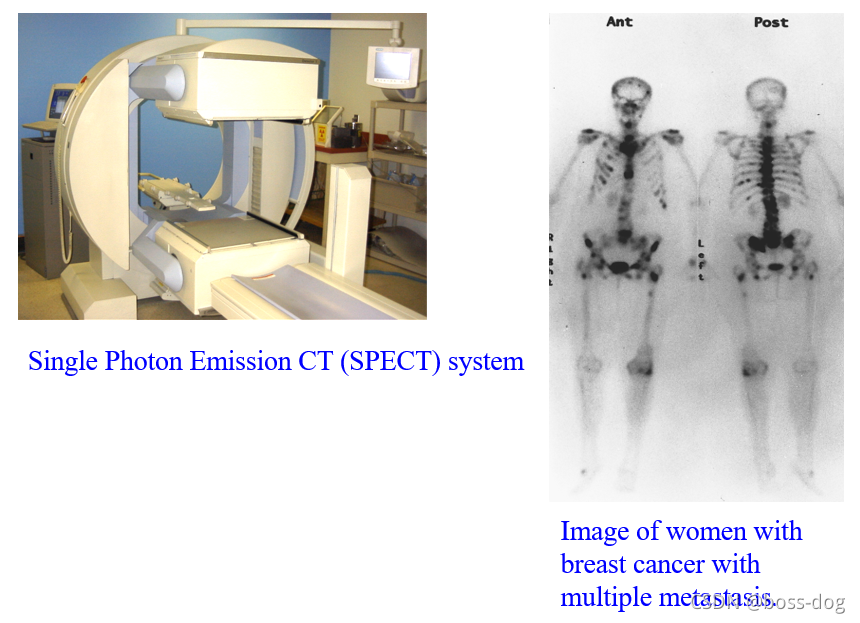

4.核素成像(Radionuclide imaging)。有核辐射,需要采用高能量的X光或者伽马光子;应用领域如单光子平面或成像(Planar single photon imaging)、单光子发射的CT(Single Photon EmissionCT,SPECT)、正电子发射成像(Positron Emission Tonography),这三类都是需要通过往人体里面进行静脉注射一种核素,这种核素需要释放出光子或者释放出正电子来回到它的稳态,如果释放出光子,这光子高能光子穿过人体就会被探测器接收到,然后用来做成像。

Gamma Camera/Scintillation Camera(核素成像)

心脏成像